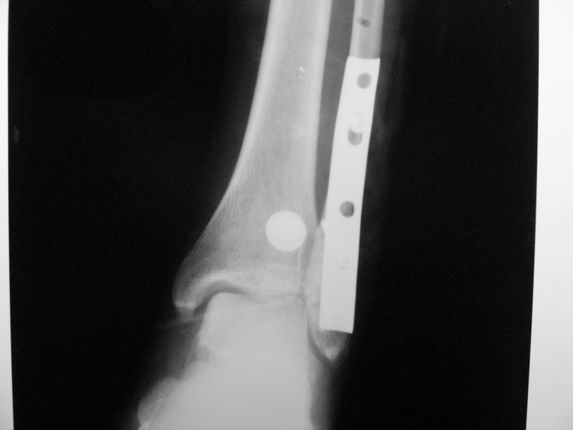

Уважаемые коллеги! Как и обещал, представляю плоды своей работы. Хвалиться особо нечем. Пошли задним

доступом сначала к м/берцовой кости, благодаря смещению линию перелома удалось сразу дифференцировать и по ней узким долотом (без молотка) мобилизовали отломки. Затем выделили задний край, там было проще пройти по линии перелома. Далее пластина по задней поверхности в дистальный отломок, винт проксимальнее пластины и дистрактором с трудом растянули отломки, ощущение было идеальной репозиции м/берцовой кости( доступен осмотр по задней и наружной поверхности), далее винты стандартно. Кстати, положение больной на боку: очень неудобно, но по-другому потом не повернуть на спину, чтобы сделать снимки в стандартных проекциях (ЭОПа нет). Затем дистрактор (два полукольца, спицы), репозиция заднего края, спонгиозный винт с шайбой, слишком проксимально, поэтому + еще один. Доступ к дельтовидной связке: рубец в передней порции, частично иссечен, шов. В общем, длительность операции 3,5 часа, а сказать, что все задуманное получилось, не могу.